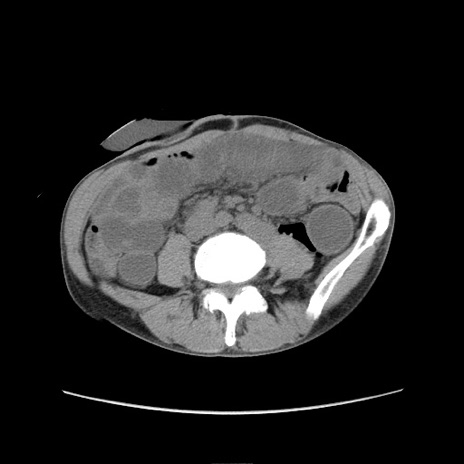

症例11(横断像)

【症例】 60歳代男性

【主訴】 下腹部痛

【現病歴】 本日夜中より下腹部痛の症状認め、受診。

【既往歴】 膀胱癌(膀胱全摘+尿管皮膚瘻術) 、胃癌術後

【身体所見】 BT 35.3℃、PR 58/min、BP 136/98mHg、腹部平坦、軟、腸蠕動音±、ストマ留置あり、左上腹部~正中部に圧痛あり、反跳痛なし。

【データ】WBC 5100、CRP0.01